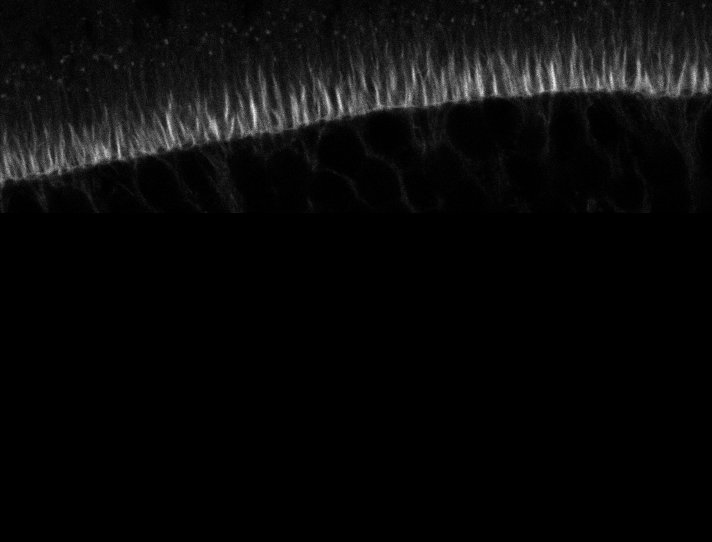

Healthy Retina

Unhealthy Retina

Healthy Eye